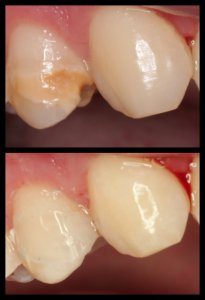

ΠΡΟΣΘΕΤΙΚΕΣ ΑΠΟΚΑΤΑΣΤΑΣΕΙΣ ΜΕ ΣΥΝΔΥΑΣΜΟ ΛΕΥΚΑΝΣΗΣ, ΣΥΝΘΕΤΩΝ ΡΗΤΙΝΩΝ ΚΑΙ ΟΛΟΚΕΡΑΜΙΚΩΝ ΟΨΕΩΝ ΚΑΙ ΣΤΕΦΑΝΩΝ